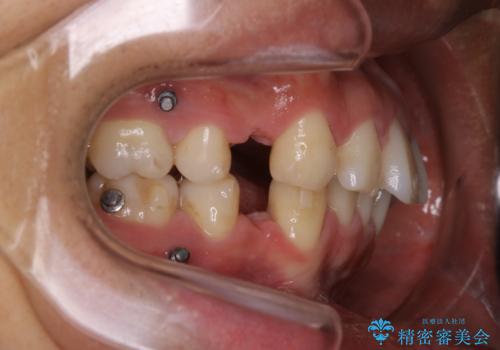

矯正中は汚れが付きやすいため、着色がとても多く付いていました。

抜歯したスペースや装置の周りの磨き方などとても難しため、定期的にクリーニングをおすすめします。